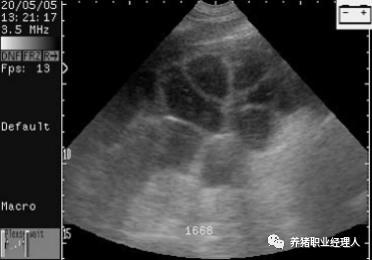

至少要发现3个不同的胚囊,才可判断为妊娠。

扫描配种第24天的母猪,大的胚胎囊可以很容易的看到。